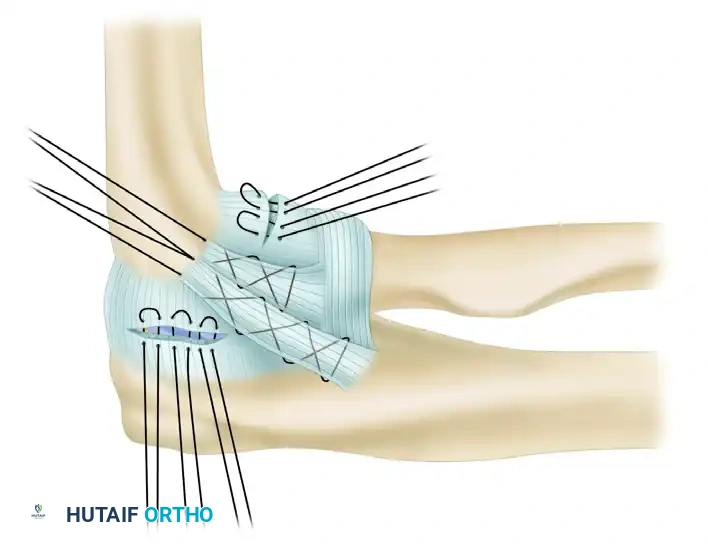

5. Graft Harvest and Passage

The palmaris longus tendon is the graft of choice due to its accessibility and biomechanical properties. If absent, a strip of triceps fascia or a gracilis autograft may be utilized.

* Harvest the graft and prepare the ends with running locking sutures (e.g., #2 non-absorbable suture).

* Pass the graft through the prepared ulnar tunnel.

* Create a "yoke stitch" to secure the graft upon itself at the ulnar insertion, ensuring a low-profile and secure anchor point before passing the limbs proximally toward the humerus.

6. Humeral Tunnel Preparation and Isometry

Identifying the isometric point on the lateral epicondyle is paramount.

* A tunnel is made in the humerus at the isometric origin.

* The primary entry hole is expanded in a posterosuperior direction to emerge posterior and superior to the point of isometry.

* A second humeral tunnel is drilled to exit posterior and inferior from the common entry site, creating a V-shaped or Y-shaped intraosseous pathway.

7. Graft Tensioning and Final Fixation

The two limbs of the palmaris longus tendon are drawn proximally and introduced into the humeral tunnels.

* The graft is tensioned with the elbow held in approximately 30 to 40 degrees of flexion and the forearm in full pronation. Pronation is critical as it closes the lateral joint space and reduces the posterolateral subluxation.

* Apply a varus stress to ensure the joint is fully reduced while tensioning.

Once optimal tension is achieved, the palmaris longus tendon limbs are drawn through the ulnar and humeral tunnels and tied to themselves after recrossing the joint. This figure-of-eight or docking configuration provides a robust, anatomic reconstruction of the LUCL. The native capsular flaps and common extensor origin are then meticulously repaired over the graft to provide additional dynamic stability.